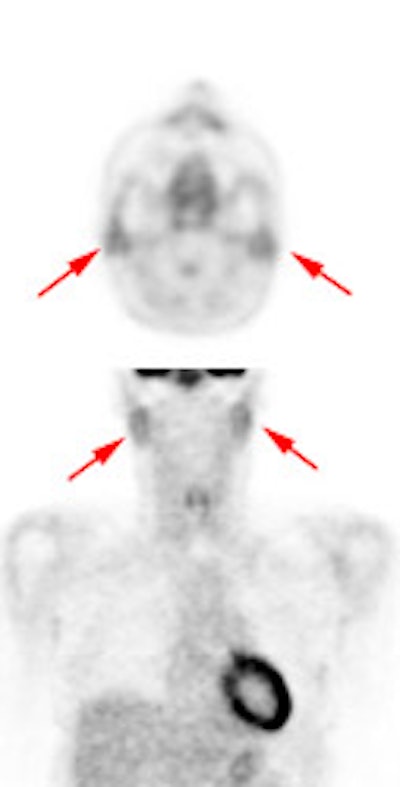

The tonsils are constantly exposed to antigens causing carious

degrees of physiologic inflammation [220]. Low to moderate FDG

uptake occurs in the lingual and palatine tonsils and at the base

of the tongue because of physiologic activity associated with the

lymphatic tissue in Waldeyer's ring [41]. However, tonsil uptake

can be high (SUV 3.11 (lingual) to 3.48 (palatine)) [103],

however, physiologic uptake is typically symmetric and asymmetric

uptake should be regarded as suspicious for malignancy [220].

There is usually uptake in the lymphoid tissue of Waldeyer's ring

[4]. The soft palate can also show tracer uptake [103]. Variable,

but typically low, uptake can be seen in the salivary glands which

secrete low amounts of glucose [41]. The parotids glands also show

mild, symmetric tracer uptake. Due to this physiologic activity,

low grade malignant lesions in the salivary and parotid glands may

be obscured [157]. Additionally, PET imaging is not able to

accurately differentiate benign from malignant parotid lesions as

benign tumors such as pleomorphic adenoma, oncocytoma, and Warthin

tumor are known to be FDG avid [312].

|

Head and neck activity: The images below show typical uptake in the tonsils (black arrows), submandibular glands (blue arrows), and parotid glands (red arrows) |